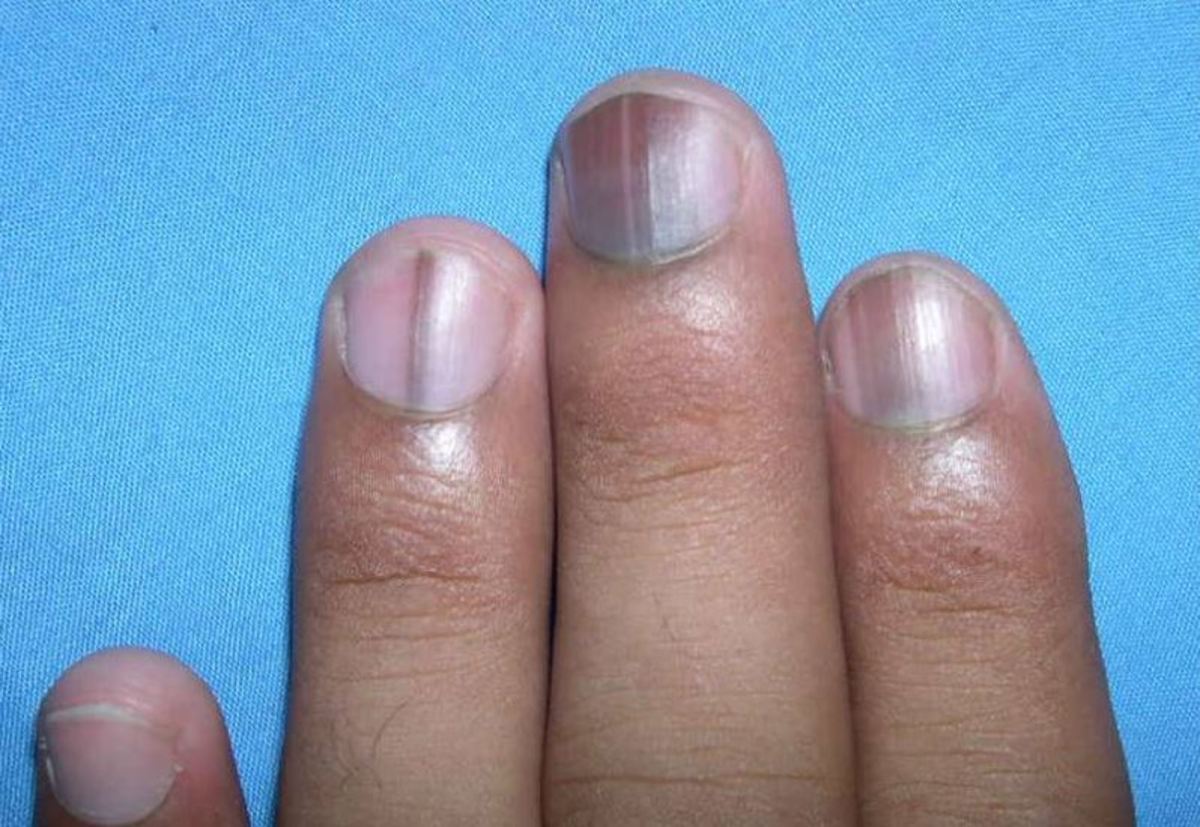

Αλλάζουν όλα στο Αλτσχάιμερ: Τεστ με 90% επιτυχία ακόμα και στα αρχικά στάδια της νόσου!

Επιστήμονες στην Ιαπωνία και στην Αυστραλία ανέπτυξαν μια απλή εξέταση αίματος, που μπορεί να ανιχνεύσει έγκαιρα τη συσσώρευση της τοξικής πρωτεΐνης βήτα αμυλοειδούς, η οποία συνδέεται με την εμφάνιση της νόσου Αλτσχάιμερ στον εγκέφαλο. Η διεθνής επιστημονική κοινότητα χαρακτήρισε το επίτευγμα ένα σημαντικό και ελπιδοφόρο βήμα, προκειμένου να υπάρξει επιτέλους ένα τεστ αίματος για τη διάγνωση της άνοιας.